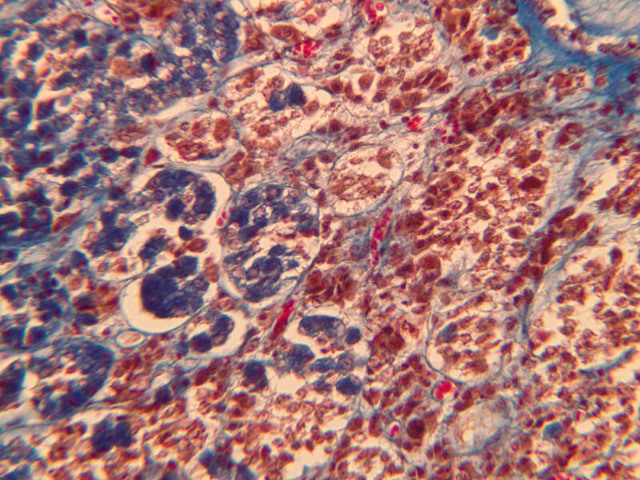

The medulla is composed of large epithelioid cells, arranged in small groups or cords which are separated by blood vessels. Usually, several large veins mark the center of the medulla. When fresh adrenal gland is incubated in solutions of chromium salts (as was the specimen on slide B-61), brownish precipitates form in the cells of the medulla-- hence, the name chromaffin cell (B-61, chromaffin [2.5x, 10x, 20x, 40x] [2.5x, 10x, 20x, 40x-labeled]). The more darkly stained chromaffin cells are known to contain norepinephrine, the less darkly stained cells, epinephrine. In essence, chromaffin cells are specialized postganglionic sympathetic neurons. How does the ultrastructure of these cells differ from that of the secretory cells of the adrenal cortex?